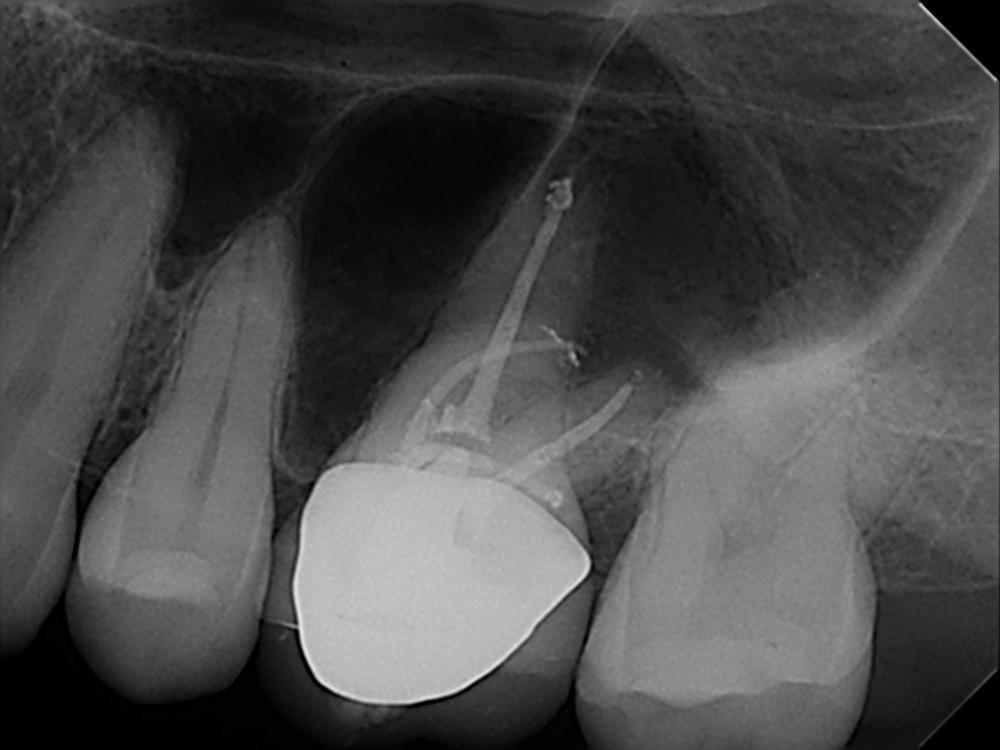

The patient was referred to our endodontic practice for evaluation and treatment of tooth 36. Clinically #36 had MOD composite restoration, a negative response to cold, and tenderness to percussion. Pre-op x-ray revealed #36 had a small periapical radiolucency associated with the Mesial root and a moderate size associated with the Distal root. Pulpal Necrosis with Symptomatic Apical Periodontitis. Endodontic diagnosis: Tooth #36 was accessed, located MB, ML, and DB and DL canals. Canals instrumented with EdgeFile X7 rotary files using a crown down technique. Pre-Op – James A. Wealleans, D.M.D, American Board Certified Endodontist, Adj Professor, Clinician Sydney, Australia

Working lengths were determined via apex locator followed by radiographic confirmation. The canal system was obturated with bioceramic sealer (BUSA, BC Sealer). The access was immediately restored with a fiber reinforced dual cure core material. Sequence of files for ‘crowndown’ (with MAF sizes) X7s 25.06 to resistance, then 20.06 to resistance, then 25.06 to resistance. Working length hand file to 15, 17.04 if necessary, 30.04, 35.04, 40.04. For this case, my final rotary file was a 40.04 at 500 RPM and 2.6 N/cm torque. Post Obturation Final